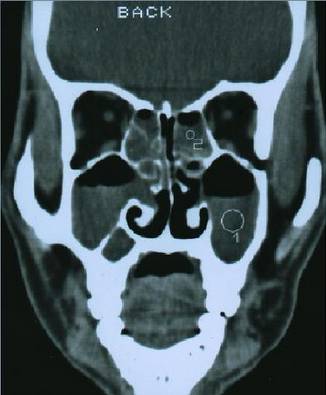

2、影像学检查:CT扫描显示窦口鼻道复合体或鼻窦粘膜病变。

- 副鼻窦X线检查,CT(冠状位、轴位)检查已常规应用。

正常鼻窦CT

鼻窦炎轴位CT

鼻窦炎冠状CT